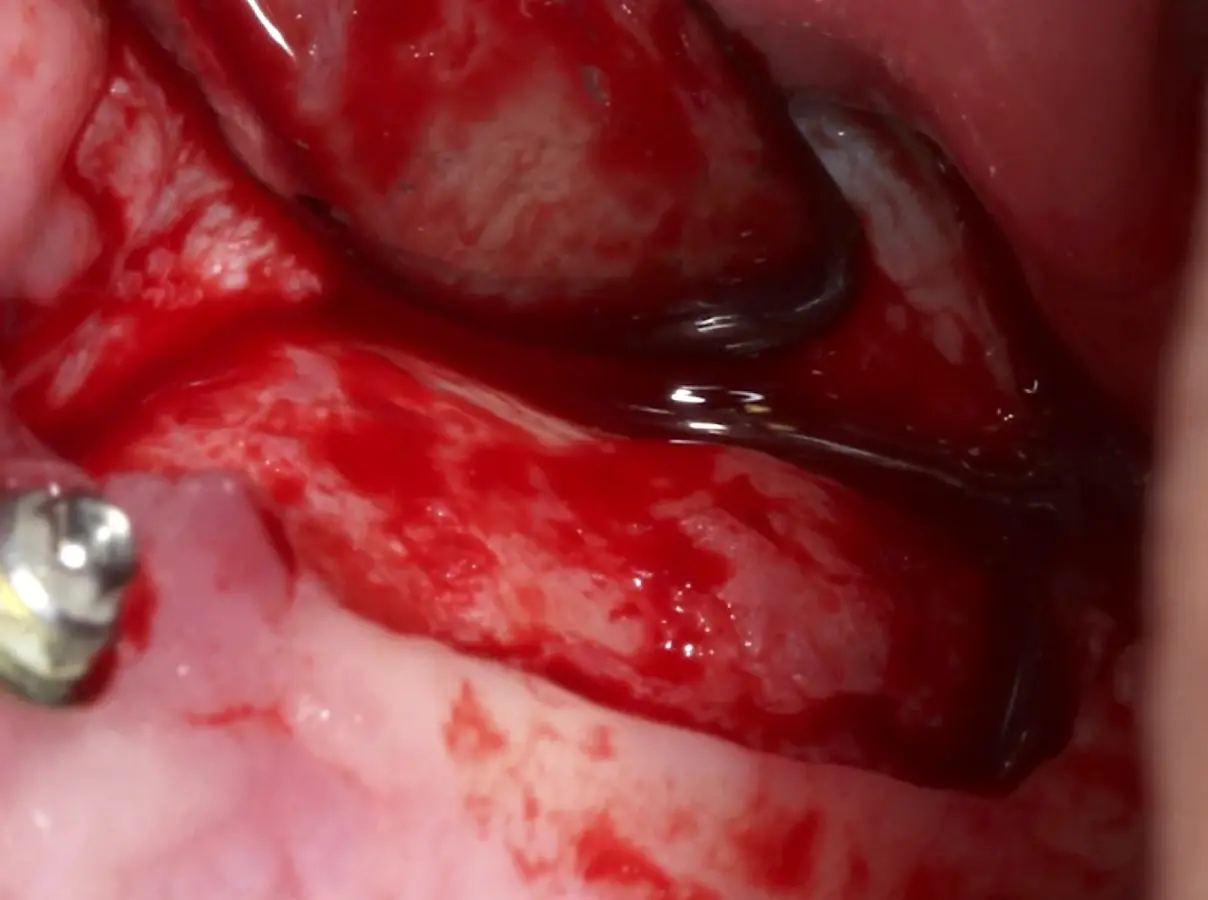

Se inicia la elevación de la membrana de Schneider con el inserto redondeado no cortante en forma de disco, empleando movimientos suaves. El levantamiento puede complementarse con elevadores convencionales, siguiendo la dirección mesiodistal. La fase de desprendimiento inicia con el piso y sigue hacia la pared mesial para terminar, y de ser necesario, hacia la pared posterior. Existen diversos insertos con angulaciones y longitudes para mayor accesibilidad16 (Figura 1).

Figura 1. Incisión y levantamiento de colgajo a espesor total.

Figura 15. Incisión supracrestal y decolado a espesor total del lado izquierdo.